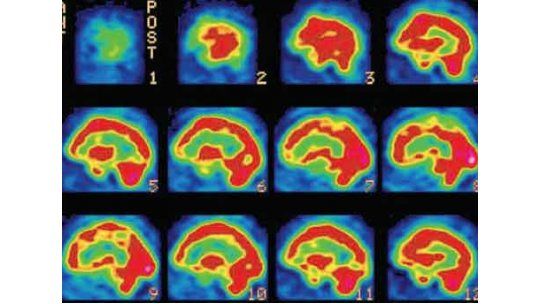

Un estudio revela que los consumidores de cannabis tienen el cerebro encogido, según da cuenta este martes el portal La Información en base a una investigación científica.

Según un estudio publicado en The Proceedings of the National Academy of Science (PNAS), un usuario habitual de cannabis tiene, de media, menos materia gris en su vórtice frontal, una región vital en el sistema de motivación, recompensas, toma de decisiones y adicción.

Los resultados muestran que los usuarios crónicos tienen menor volumen cerebral en la corteza orbitofrontal (OFC), una parte del cerebro asociada con la adición pero también con la conectividad cerebral.

El equipo estudió a 48 adultos consumidores de marihuana y 62 no usuarios, que fueron también controlados por su consumo de tabaco y alcohol.

El promedio de consumo de los investigados era de tres veces al día. Las pruebas muestran que los consumidores de marihuana tenían menor coeficiente intelectual.

El uso crónico de la marihuana inicia un proceso complejo que permite a las neuronas adaptarse y compensar el volumen de materia gris más pequeña, pero se necesitan más estudio para determinar si estos cambios vuelven a la normalidad con el consumo discontinuo de marihuana, si efectos similares están presentes en los consumidores ocasionales frente a los crónicos y si estos efectos son el resultado directo del consumo de marihuana o un factor que predispone.